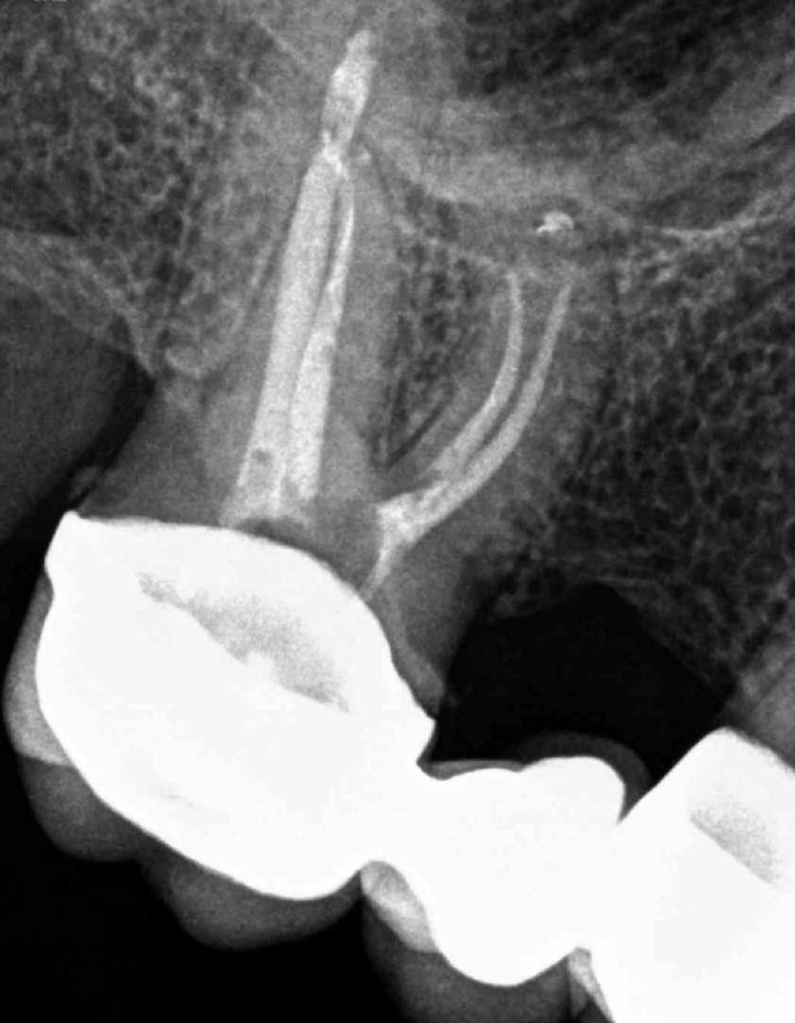

Endodoncias a traves de coronas

20 molar superior a traves de corona